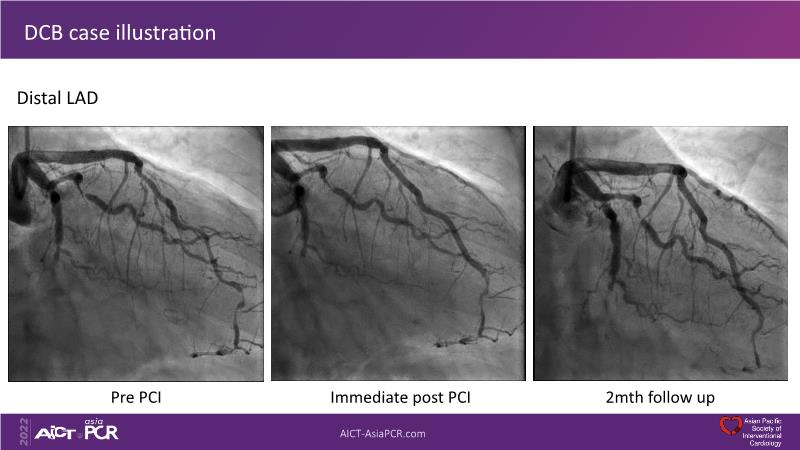

- To learn the utility of the DCB for PCI in a variety of lesion and patient subsets

- To understand the evidence and outcomes of this DCB in real world patients